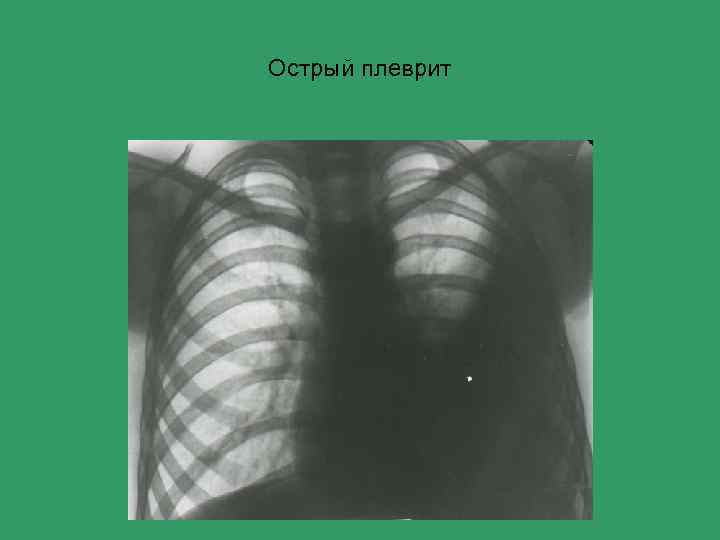

Острый плеврит